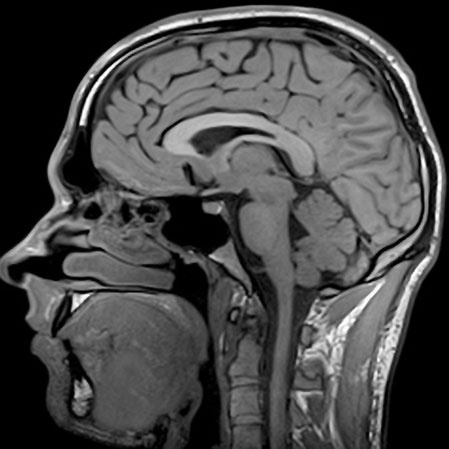

7.7. Как работает МРТ?

Современная медицина уже никого не удивляет тем, что может увидеть человека насквозь. Но вы только представьте, сколько различных методов изобретено: УЗИ, рентген, МРТ. Пожалуй, самым совершенным является последний, о нем и поговорим. МРТ позволяет создавать трехмерное изображение внутренностей человека чуть ли не в полный рост, при этом никакого вредного воздействия не оказывает! Так каков его принцип действия?

Магнитно-резонансный томограф представляет из себя огромный магнит, с очень сильным полем. В самых сильных моделях оно может быть в 100 000 раз больше магнитного поля Земли! Так вот, ядра наших атомов сами являются маленькими магнитиками (потому что у них есть спин, они как бы вращаются и как бы являются малюсенькими электротоками, ведущими себя, как электромагнит). Соответственно они могут взаимодействовать с внешним магнитным полем и поворачиваются либо вдоль поля, либо против. Следует отметить, что так ведут себя только ядра с нечетным количеством протонов и нейтронов. Но все МРТ настроены на повороты ядер водорода, который содержится в большом количестве в организме в составе воды и других соединений.

Если облучить ядро электромагнитной волной определенной частоты, то оно может поглотить ее энергию и повернуться на 90 или 180 градусов, в зависимости от частоты. Через некоторое время ядро релаксирует в свое исходное состояние и излишек энергии излучает в виде электромагнитной волны. Это излучение принимается антеннами по сути как обычное радио, и если облучать ткани, то по интенсивности «отклика» можно понять, много там ядер водорода или нет. В разных тканях его разное количество, поэтому на изображении отчетливо видна разница между ними.

Но все же это достаточно дорогой и технически сложный способ наблюдения за внутренностями человека. Дело в том, что частота поглощения зависит от поля. Если бы везде поле было одинаковым, то поглощение и излучение происходило бы везде, мы бы не узнали, откуда пришел сигнал, и картинки не получилось бы.

Поэтому на практике делают так. Включают основной магнит, радиоизлучатель и так называемые градиентные поля. Они добавляются или вычитаются из поля основного магнита, делая его неоднородным. Из-за этого резонансное поглощение энергии происходит не везде, а только в маленьком участочке. Оттуда летят радиоволны и уже принимаются антеннами. Изменяя градиентные поля, мы передвигаем место резонанса, как бы сканируя тело, и получаем некий «отклик» из каждой точки тела.

В разных тканях содержится разное количество водорода (в воде и других соединениях), поэтому мы получаем разный отклик и можем восстановить картину внутренних органов. Так же время релаксации тоже различно для разных тканей! Во многих исследованиях измеряют и его, получая очень точную картину.